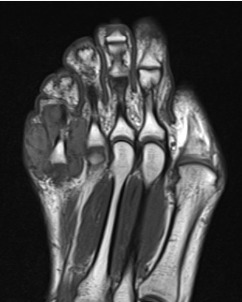

Tumor de células gigantes da bainha de tendão: tumor benigno de partes moles mais comum da mão, afeta face, palmar e dedos, também frequente nos pés. Devido à proximidade dos tendões, podem causar incômodo no movimento e dor.